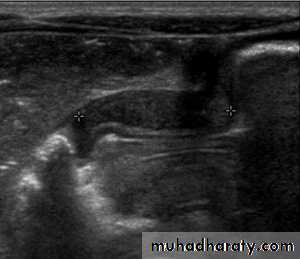

Pyloric stenosis is relatively common and has a male predilection (M:F ~ 4:1), and is more commonly seen in Caucasians 4. It typically occurs between the 4-8 weeks of life. There may be a positive family history. Incidence of hypertrophic pyloric stenosis is approximately 2-5 per 1,000 births per year in most white populations,Hypertrophic pyloric stenosis refers to idiopathic thickening of gastric pyloric musculature which then results in progressive gastric outlet obstruction

In a normal situation, the pyloric muscle thickness (diameter of a single muscular wall on a transverse image) should normally be less than 3 mm (most accurate 3) and the length (longitudinal measurement) should not exceed 15 mm.